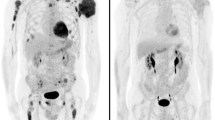

Concerning patients with only negative densitometry (HU < 0) LBLs, the first patient (N°16) with one osteolytic lesion at iliac crest bone presented total PCs infiltration of bone marrow and anemia calling for starting therapy. The second patient (N°17) with only one osteolysis at L5 was otherwise classified as high-risk smoldering MM. At 10-month follow-up, the same CT lesion showed positive densitometry over other bone lesions (Fig. 1). This finding was associated with total PC bone marrow infiltration and anemia requiring starting therapy. The third patient (N°18) with six osteolytic lesions of spine had also 50% of malignant PCs in bone marrow. Due to PET and MRI negativity, this pattern of osteolytic lesions was initially considered of uncertain clinical significance, and patient started close monitoring. Ten months later, in presence of a biochemical progression, a second WB-LDCT showed an increased in number and size of previously negative densitometries LBL and the development of other areas with positive densitometry.

Patients with negative HU LBL showed low signal in STIR and DWI sequences, high signal in T1w images low ADC values (mean 363 × 10−6 mm2/s; SD ± 0.153) and low SUV max values (mean 1.03; SD ± 0.42) (Fig. 2 and supplementary Fig. 1; supplementary Fig. 2 reports another case with the same characteristics), while patients with positive HU LBL showed low T1w signal and high signal in STIR and DWI sequences, higher ADC values (mean 868 × 10−6 mm2/s; SD ± 0.208) and SUV max values (mean 3.54; SD ± 1.63) (Fig. 3). Statistical analysis based on linear regression with robust standard errors accounting for dependence between observations from the same patient confirmed that the mean ADC values and log-transformed SUV max values were strongly significantly different in the two groups (z = 10.7, p value < 0.001 for ADC; z = 10.793, p value < 0.001 for SUV max). Figures 4 and 5 display the relationships between densitometry and ADC and densitometry and SUV max, respectively.

According to HU densities of LBL, two different patterns of lytic lesions were herein demonstrated at WB-LDCT scan in MM patients, one with features of fat replacement of trabecular bone (HU < 0), the other characterized by pathological cell infiltration with tissue-like density (HU > 0). Only the infiltrative pattern was consistently captured by PET/MRI. Otherwise, WB-LDCT also detected unequivocal LBLs characterized by negative HU values, consistent with fat density, with negligible 18FDG uptake at PET and low ADC at DWI-MRI. Should only PET/MRI be taken into account in these cases, these types of lesions would have not been considered as a proof of symptomatic disease. We also demonstrated that both types of lytic lesions (i.e., those with HU < 0 and those with HU > 0) can be present at the same time in the same patient, highlighting that both conditions are consistent of symptomatic bone disease. As a matter of fact, the histological evaluation that typical negative density LBLs were characterized by infiltration of neoplastic plasma cells spreaded within adypocytes provided the formal proof of their pathological nature. Interestingly, we showed that, during follow-up, HU-negative LBLs can became HU positive with glucose avidity at PET and pathological ADC, suggesting a relationship between the two types of lesions, the fat pattern likely anticipating the infiltrative one.

The pathogenetic mechanisms that lead to the development of myeloma bone disease are well known [23,24,25,26]. Since the first evidence in animal models that the RANKL/RANK/OPG system plays a critical role in the development of osteolytic bone disease in MM, data have been accumulated that bone resorption is associated with the presence of increased numbers of osteoclasts, whereas bone formation is reduced [27]. This uncoupling of resorption and formation, in association with an increased frequency of bone remodeling units, leads to rapid bone loss and the development of osteolytic bone lesions. Myeloma cells were found closely associated with CD68-positive multinucleated osteoclasts. Osteoclasts could be found on cancellous bone surfaces and were observed to line the corticoendosteal surface [23]. More recently, many chemokines and cytokines have been demonstrated to be involved into development of lytic lesions in MM patients [28,29,30,31,32,33,34,35,36,37], suggesting that humoral pathways are dominant in orchestrating the cross-talk between neoplastic plasma cells and osteoclasts. This hypothesis has been suggested by Dalla Palma et al. [38], who showed that MM patients with high burden of osteolytic lesions recognized by PET/CT are mostly characterized by high amounts of BM concentrations of CCL3 (MIP1a) and CCL20 (MIP3a), whereas BM DKK-1 levels were mostly associated with the presence of focal lesions on MRI in MM patients. In this quite heterogeneous landscape, the mechanisms according for the emergency of lytic lesion with HU < 0 values and fatty density is a matter of debate. The observation we provided that mean diameters of negative HU LBLs were significantly lower (11.09 mm ± SD 4.45 vs 17.36 mm ± SD 13.24) than that of infiltrative lytic lesions might suggest a particularly high cytokine/chemokine-secreting plasma cell clone. Alternatively, one might suggest that negative HU LBLs might represent an early stage, which anticipates a massive plasma cell infiltration. Data from one patient reported in this study (N°17) who was initially characterized by the presence of fatty lytic lesions only (HU − 47.7), then becoming within 10-month follow-up larger and featured by cell proliferation (HU + 29.5) are in line with the above interpretation (Fig. 1). Histological evaluation of this kind of HU < 0 lesion unequivocally demonstrated its pathological nature, characterized by a spread infiltration of neoplastic plasma cells, within a fatty background lacking bone structures, with accumulation of osteoclasts at residual bone surface (Fig. 6).